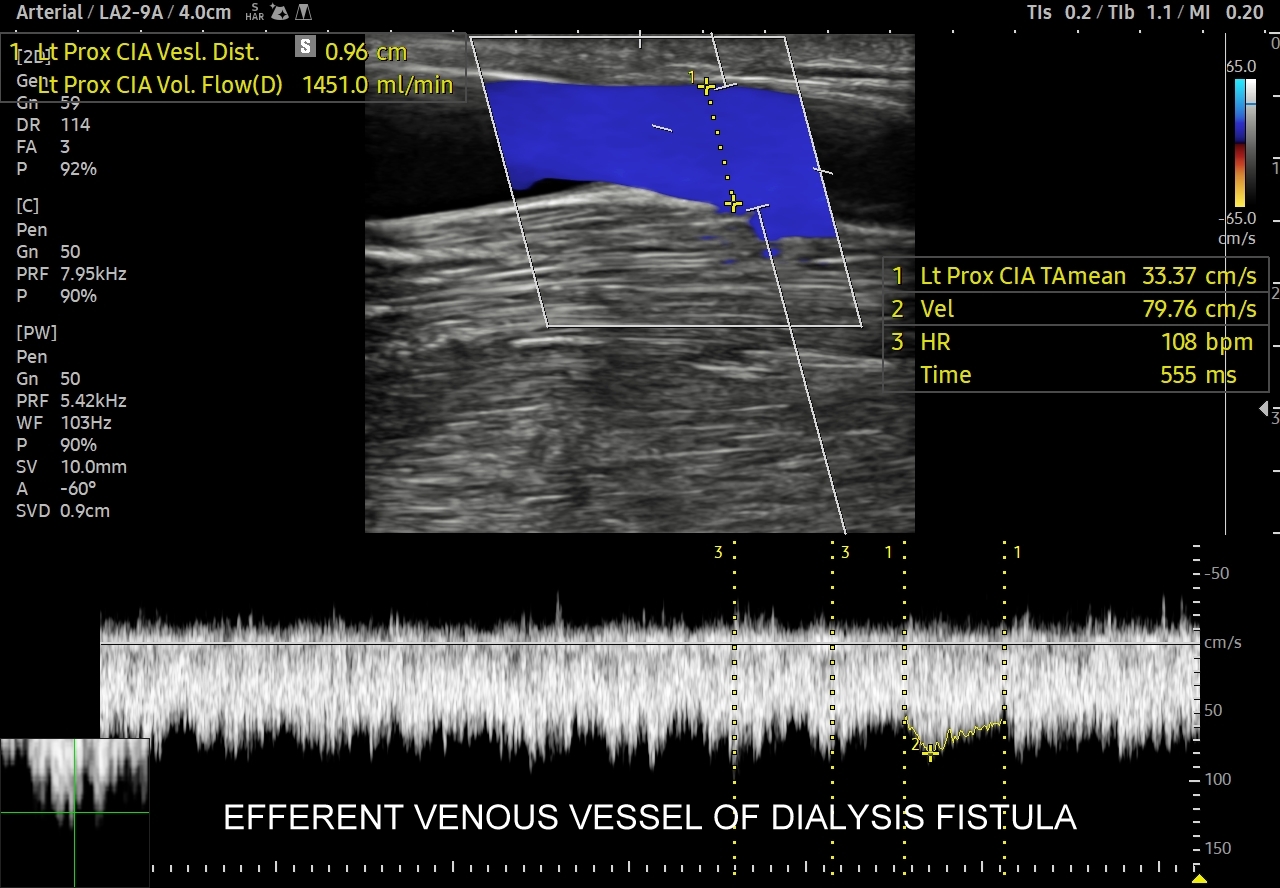

Jak oceniać przetokę dializacyjną AV w badaniu sonograficznym? W prezentacji B, color-Doppler i MVI oceniamy drożność naczyń, ich szerokość, okołoprzetokowe drżenie tkanek, a w prezentacji Dopplera spektralnego objętość przepływającej krwi oraz ewentualne objawy niedrożności i zwężeń, tj. zmiany w profilu przepływu świadczące bezpośrednio lub pośrednio o powikłaniu / niepowodzeniu przetoki.

W celu oceny objętości minutowej przepływającej przez przetokę krwi wybieramy odpowiedni program w aparacie, zaznaczamy średnicę badanego naczynia oraz oznaczamy w Dopplerze spektralnym profil uśrednionego przepływu ustawiając bramkę pomiarową na szerokości całego naczynia.

W celu oceny drożności sprawdzamy profil przepływu w naczyniu tętniczym doprowadzającym, który powinien pozostać niskooporowym. W przypadku powrotu 2/3 załamkowego tętniczego profilu przepływu wysokooporowego podejrzewać można zwężenie lub niedrożność przetoki. Dopplerem spektralnym sprawdzamy również żylne naczynie odprowadzające tuż za przetoką, ale również naczynia żylne bliższe klatce piersiowej, gdyż niedrożność może wystąpić także w odcinkach żylnych oddalonych od przetoki, np. w żyłach podobojczykowych, ramienno-głowowych, czy w żyle głównej górnej.